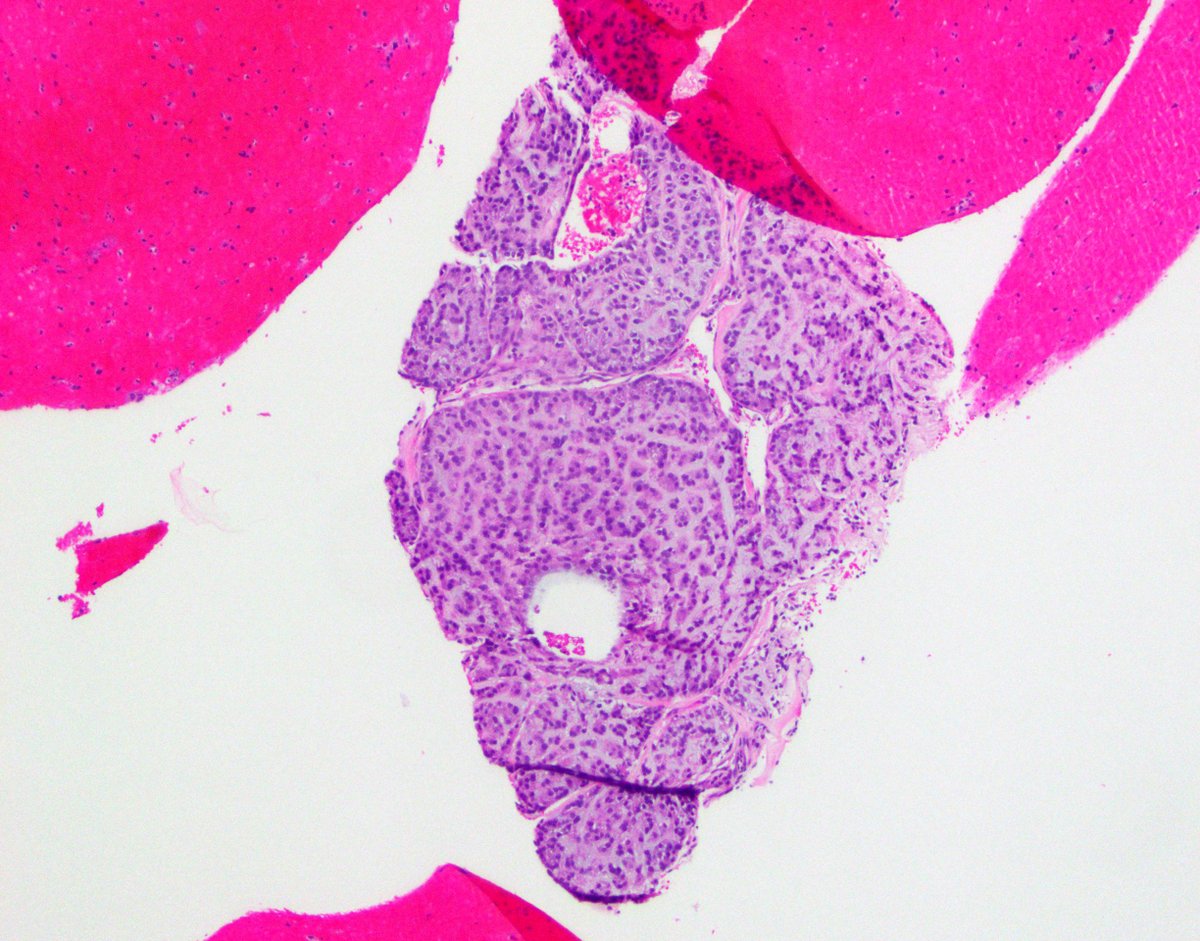

Our GI Pathology Fellowship has an unexpected opening for July 2026. Dr. Ortiz (right) and I are the program directors. We have superb cases and excellent colleagues (Drs. M. Garcia, R. Yantiss, S. Al Diffalha, O. McDonald). Send your CV to adriana.zanaty@miami.edu